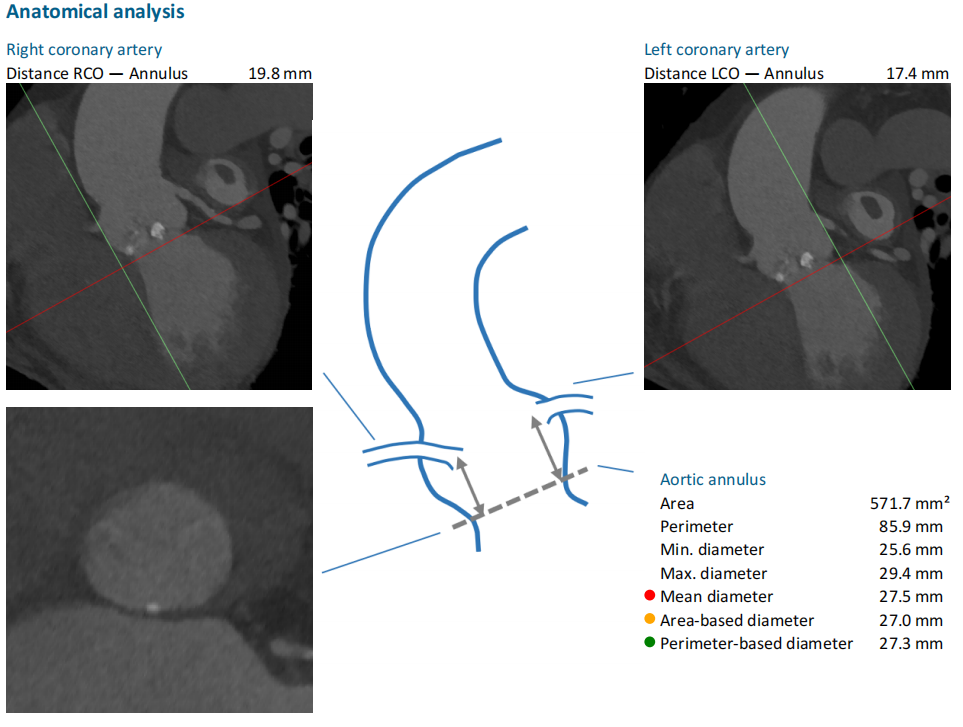

术前CT评估:

瓣环平均直径:26.8mm,左室流出道平均直径:31.2mm;

升主动脉(未见)明显扩张,心脏角度:69°;

左冠高度:12.5 mm,右冠高度:13.6 mm。

Annulus:26.8mm;LVOT:31.2mm

Sinus:27.4mm*40.7mm;STJ:32.9mm*32.9mm

升主:38.1mm*38.6mm;主动脉成角:69°

钙化积分:790